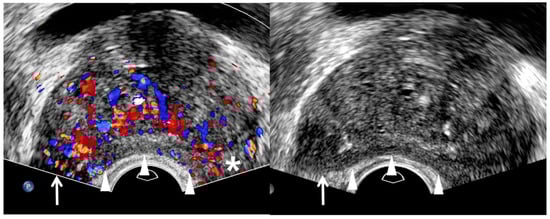

| TRUS Features | Peripheral Cancer | Transition Cancer | ||

|---|---|---|---|---|

| Insignificant Cancer | Significant Cancer | Insignificant Cancer | Significant Cancer | |

| Echogenicity | Low | Lower | High | Higher |

| Size | Small | Large | Small | Large |

| Echotexture | Homogeneous | Heterogeneous | Homogeneous | Heterogeneous |

| Margin | Smooth | Irregular | Smooth | Irregular |

| Perfusion | Low | High | NA | NA |

| Hypoechoic rim | NA | NA | Clear | Unclear |